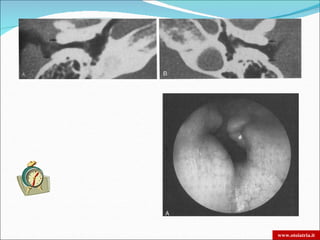

 TC: osteolisi dell’osso timpanico e della base cranica

 RM: invasione dei tessuti molli e dei forami nervosi. Meningite

OTITE ESTERNA MALIGNA DIAGNOSI  Tampone auricolare  Glicemia e VES  TC: osteolisi dell’osso timpanico e della base cranica  RM: invasione dei tessuti molli e dei forami nervosi. Meningite  Scintigrafia:  Al Gallio: + sensibile e specifica per osso e tessuti molli, ma minore risoluzione spaziale zone di diffusione meno esatte  Al Tecnezio99: si fissa sulle zone osteogeniche della distruzione osseea. La sua negatività conferma la guarigione. www.otoiatria.it